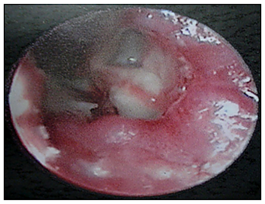

Thorough clinical examination revealed right hemiparesis, left Lateral rectus palsy suggestive of sixth cranial nerve palsy and deviation of angle of the mouth due to left Facial nerve Palsy (Lower Motor Neuron type) (Figure1). There was a palpable firm mass in the upper neck behind the angle of jaw on left side, post auricular lymphadenopathy and a positive Griesinger’s sign (Figure 2). Otoscopy revealed active mucopurulent discharge with granulations and necrotic tissue in external auditory canal and the middle ear (Figure 3). Magnetic resonance imaging and Contrast enhanced computed tomography temporal bones and neck revealed left coalescent mastoiditis with extension across the subperiostium with fluid collection involving the soft tissue of left postauricular region, extradural abscess from left petrous, basal meningitis and pontine infarct. Magnetic resonance venogram and angiogram revealed Central venous sinus thrombosis (CVST) of left sigmoid sinus, transverse and superior sagittal sinus, loss of luminal signal of left internal jugular vein at jugular bulb and decreased flow related to enhancement involving the petrous segment of the left internal carotid artery (ICA) (Figure 4).

Figure 3 Otoendoscopic picture of the left Ear showing necrotic material and granulations in the external auditory canal and the middle ear.